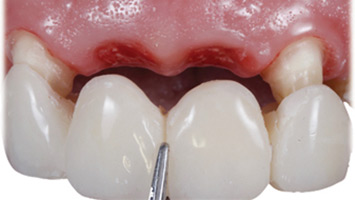

Keys for Successful Aesthetic Zone Single Implant: Case Reports

Noroozi_3Fig5 alternate text for this image

To achieve a successful aesthetic result and good patient satisfaction, implant placement in the aesthetic zone demands a thorough understanding of anatomic, biologic, surgical and prosthetic principles. The ability to achieve harmonious, indistinguishable restoration from adjacent natural teeth in the aesthetic zone is very often challenging. Placement of dental implants in the aesthetic zone is … Read more